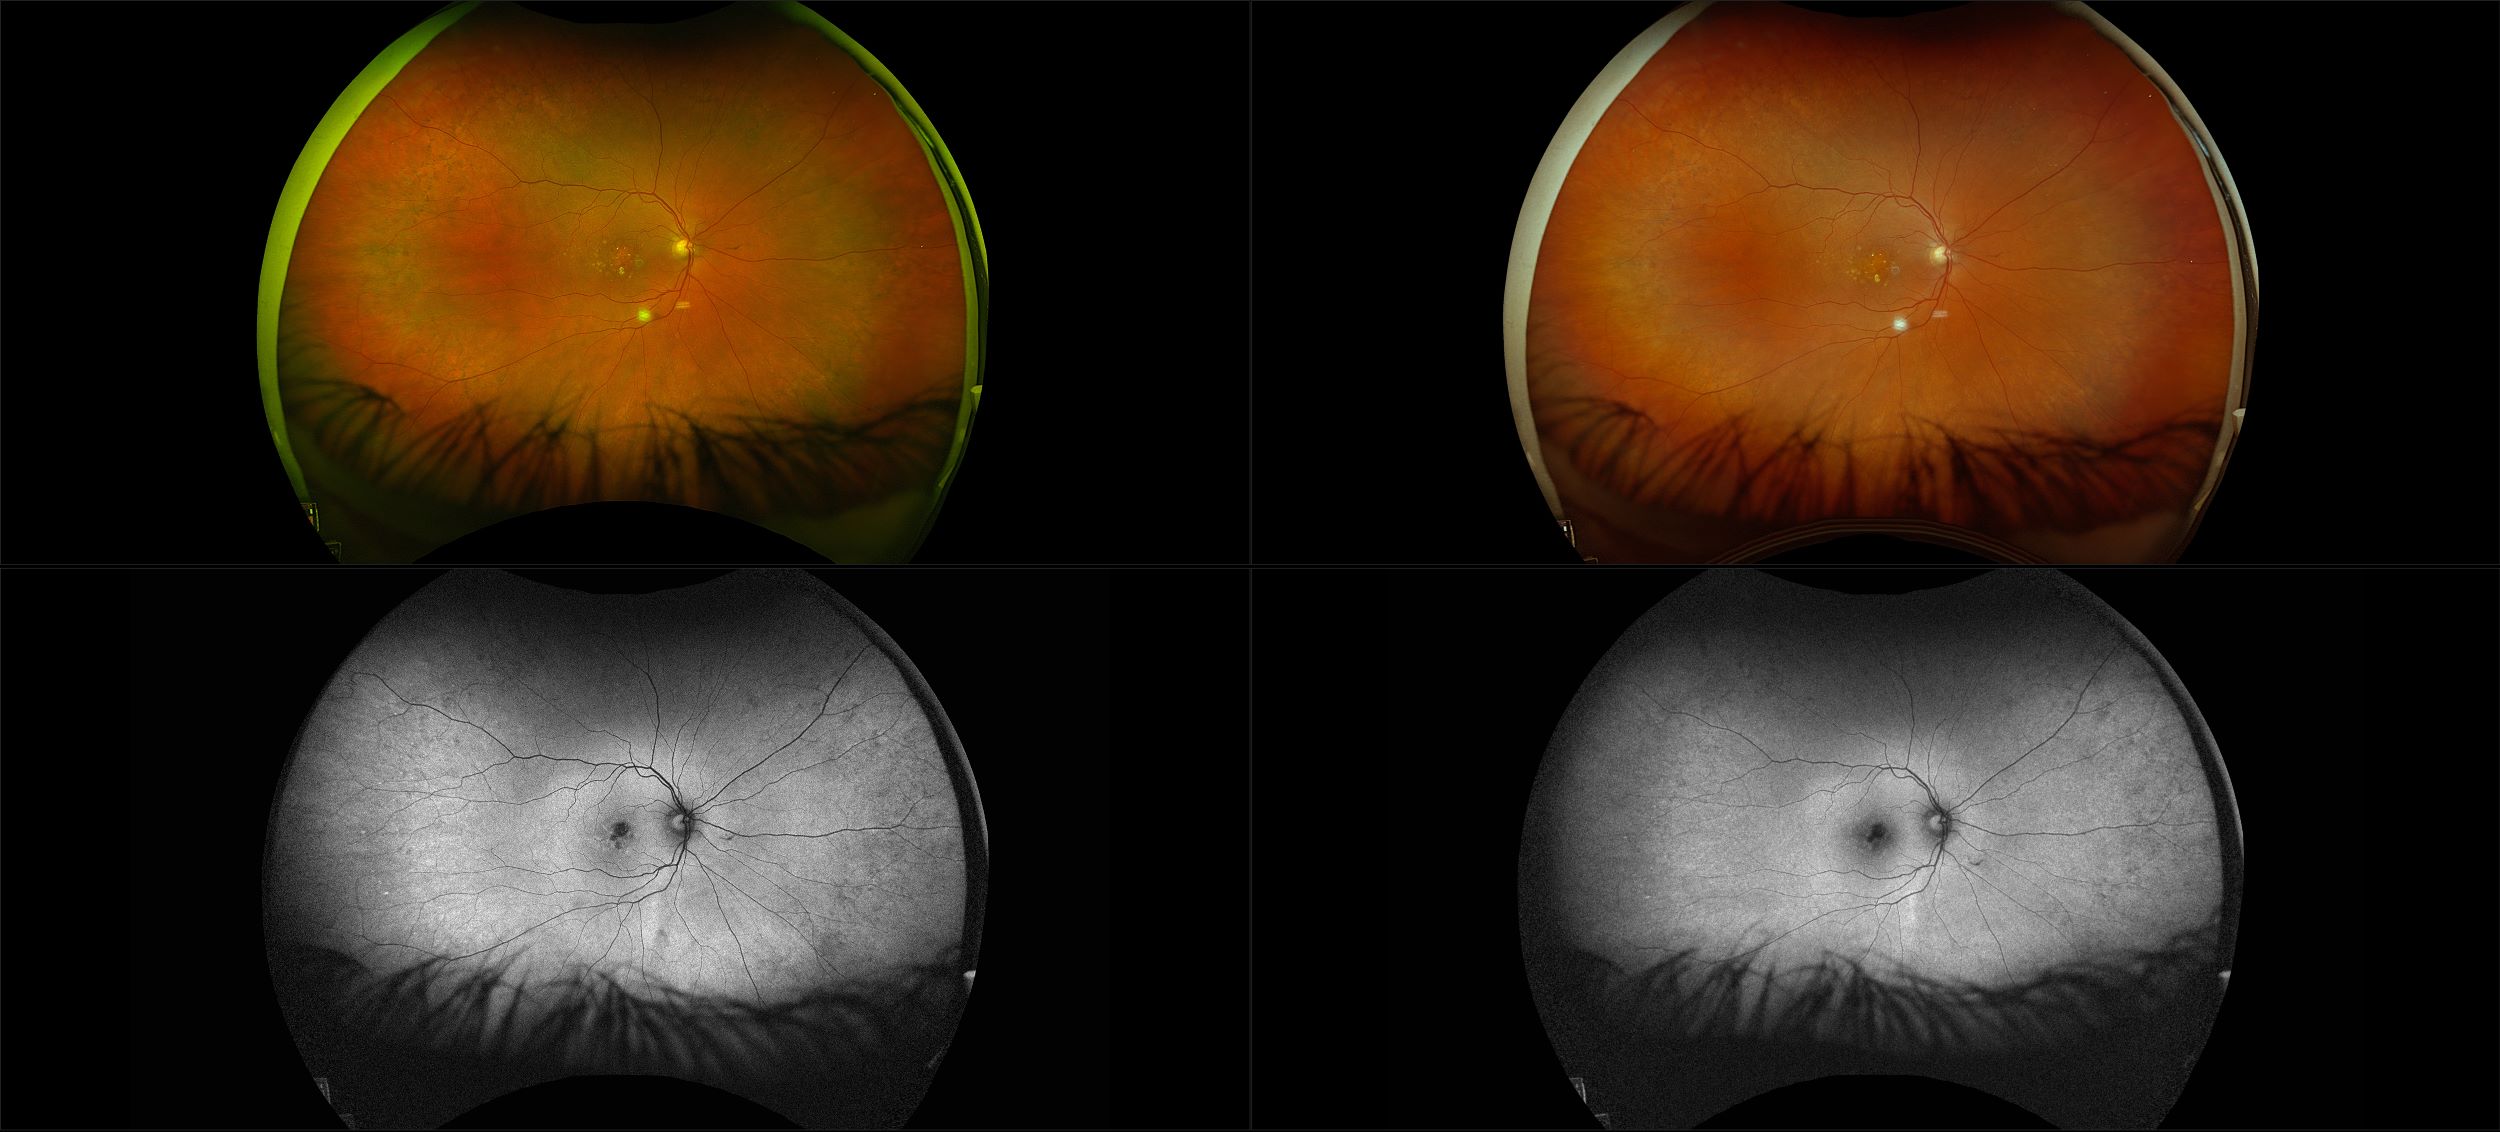

California - AMD, RG, AF

Age-related macular degeneration is found in two forms 1. Dry early form. 2. Wet (serous leakage or whole blood). Early dry form typically has drusen (usually around 63u) and RPE degeneration and only needs periodic follow-ups, intermediate dry form has large drusen (>125u) and RPE degeneration and proliferation which requires examinations every 3 to 6 months depending on the severity of the presentation.